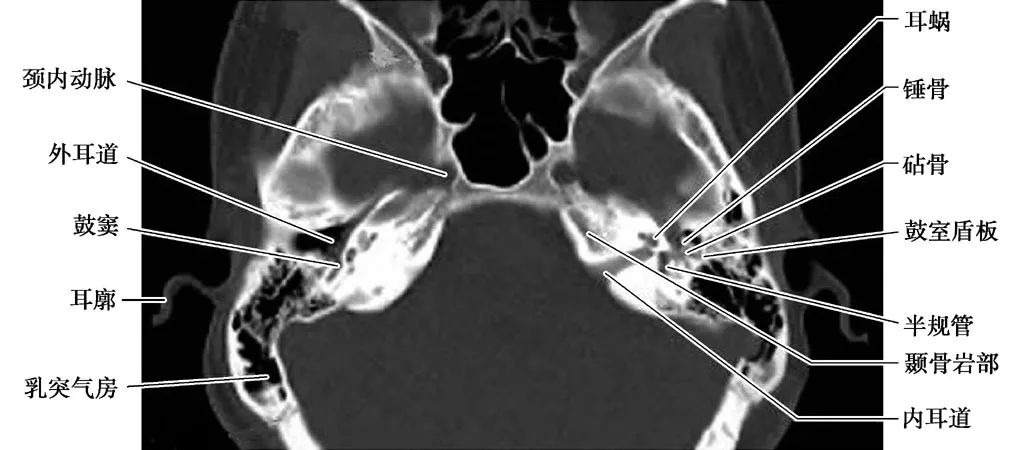

耳部及其周围的重要解剖结构 (CT横断面)

A.上骨半规管层面;B.外骨半规管层面;C.前庭窗层面;D.耳蜗层面;E.颈动脉管层面1.上骨半规管;2.弓形下窝;3.总骨脚;4.后骨半规管;5.外骨半规管;6.内耳道;7.耳蜗;8.面神经管迷路段;9.膝状神经节;10.前庭;11.上鼓室;12.乳突窦入口;13.乳突窦;14.鼓膜张肌;15.锤骨头;16.砧骨体;17.前庭窗;18.前庭导水管;19.圆窗;20.鼓岬;21.锤骨颈;22.砧骨长脚;23.面神经隐窝;24.锥隆起;25.鼓室窦;26.颈动脉管;27.咽鼓管;28.耳蜗导水管;29.颈静脉球